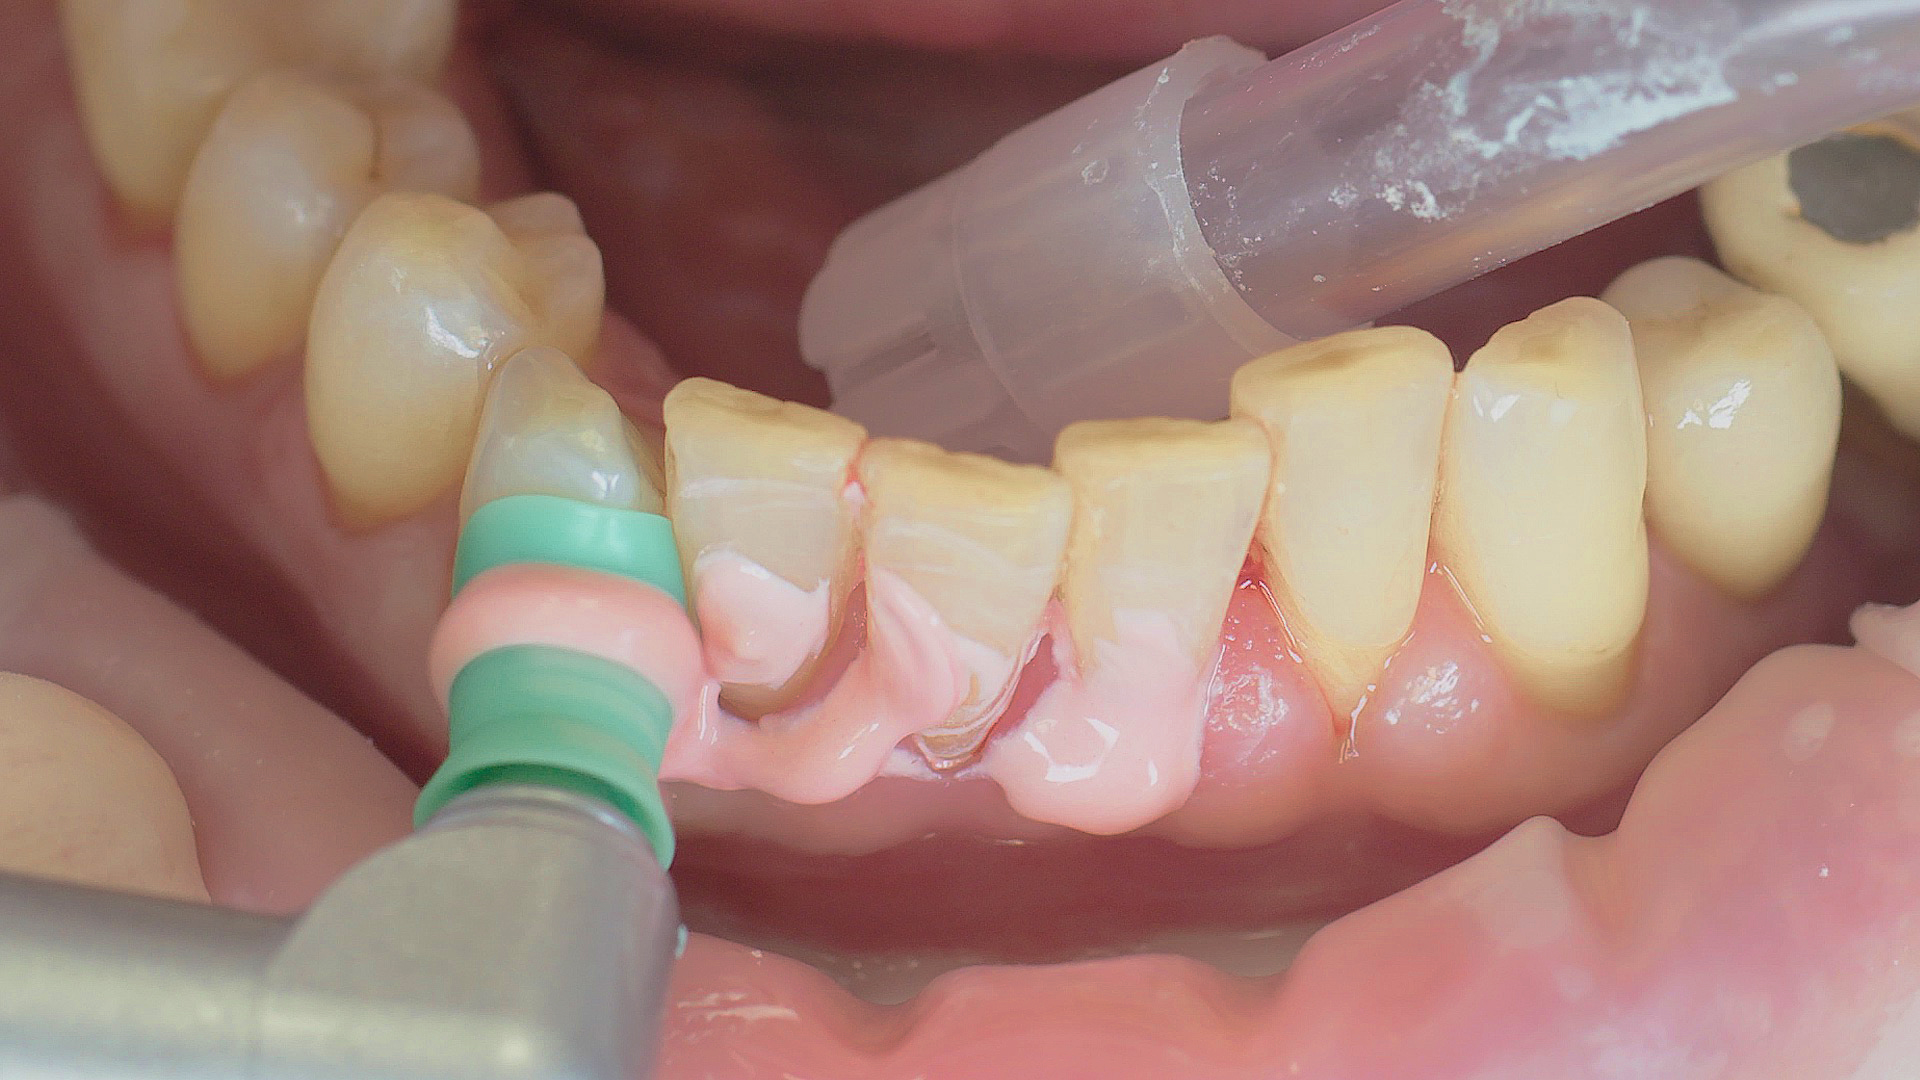

Si nécessaire, un traitement parodontal préventif est effectué. Un nettoyage dentaire professionnel contribue dans un premier temps à des conditions gingivales saines. Il permet d’éliminer le tartre (Fig. 1) et le biofilm (Fig. 2) jusque dans le sulcus gingival. En association à des consignes d’hygiène buccodentaire méticuleuses,

il élimine également à long terme le risque de récidives d'inflammation chez le patient.[15]

Dans le cadre du traitement parodontal préventif, le détartrage subgingival (debridement en anglais) est effectué à l'aide d'appareils à ultrasons et d'inserts paro spécifiques (Fig. 3). Des instruments manuels peuvent également être utilisés. En fonction de la situation, d'autres mesures, y compris chirurgicales et régénératives, peuvent s’avérer nécessaires.